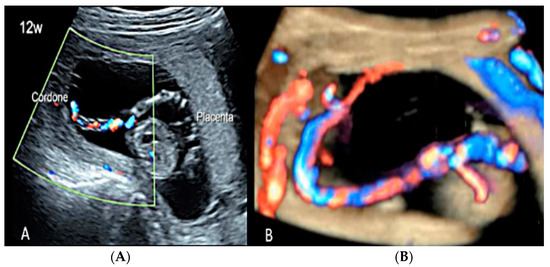

3.2. Umbilical Cord Anomalies

3.2.6. Umbilical Cord Entanglement